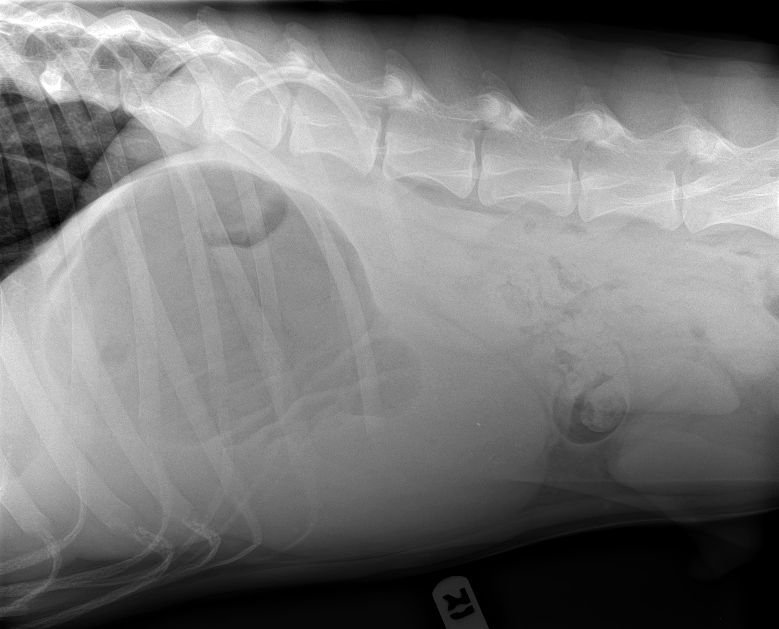

Lat D